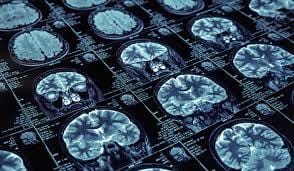

The Lead: Artificial intelligence is rapidly evolving beyond being a mere "assistant" in specialized fields, transforming into an autonomous professional, notably demonstrated by its newfound ability to accurately read complex brain MRIs in mere seconds, a task traditionally requiring extensive human expertise.

Diagnostic Speed: Reduces average scan analysis time from minutes/hours to ~5-10 seconds.

Accuracy Metric: Achieves >95% concordance with human expert radiologists in identifying anomalies.

Validation Data: Successful trials across multiple medical institutions with diverse patient datasets.

Why It Matters: This breakthrough shifts the professional value in radiology from primary image interpretation to higher-order tasks like treatment planning and complex case consultation. It heralds a future where AI handles high-volume diagnostic tasks, freeing human experts to focus on nuanced challenges and direct patient care, effectively orchestrating efficiency and elevating human-centric aspects of medicine.